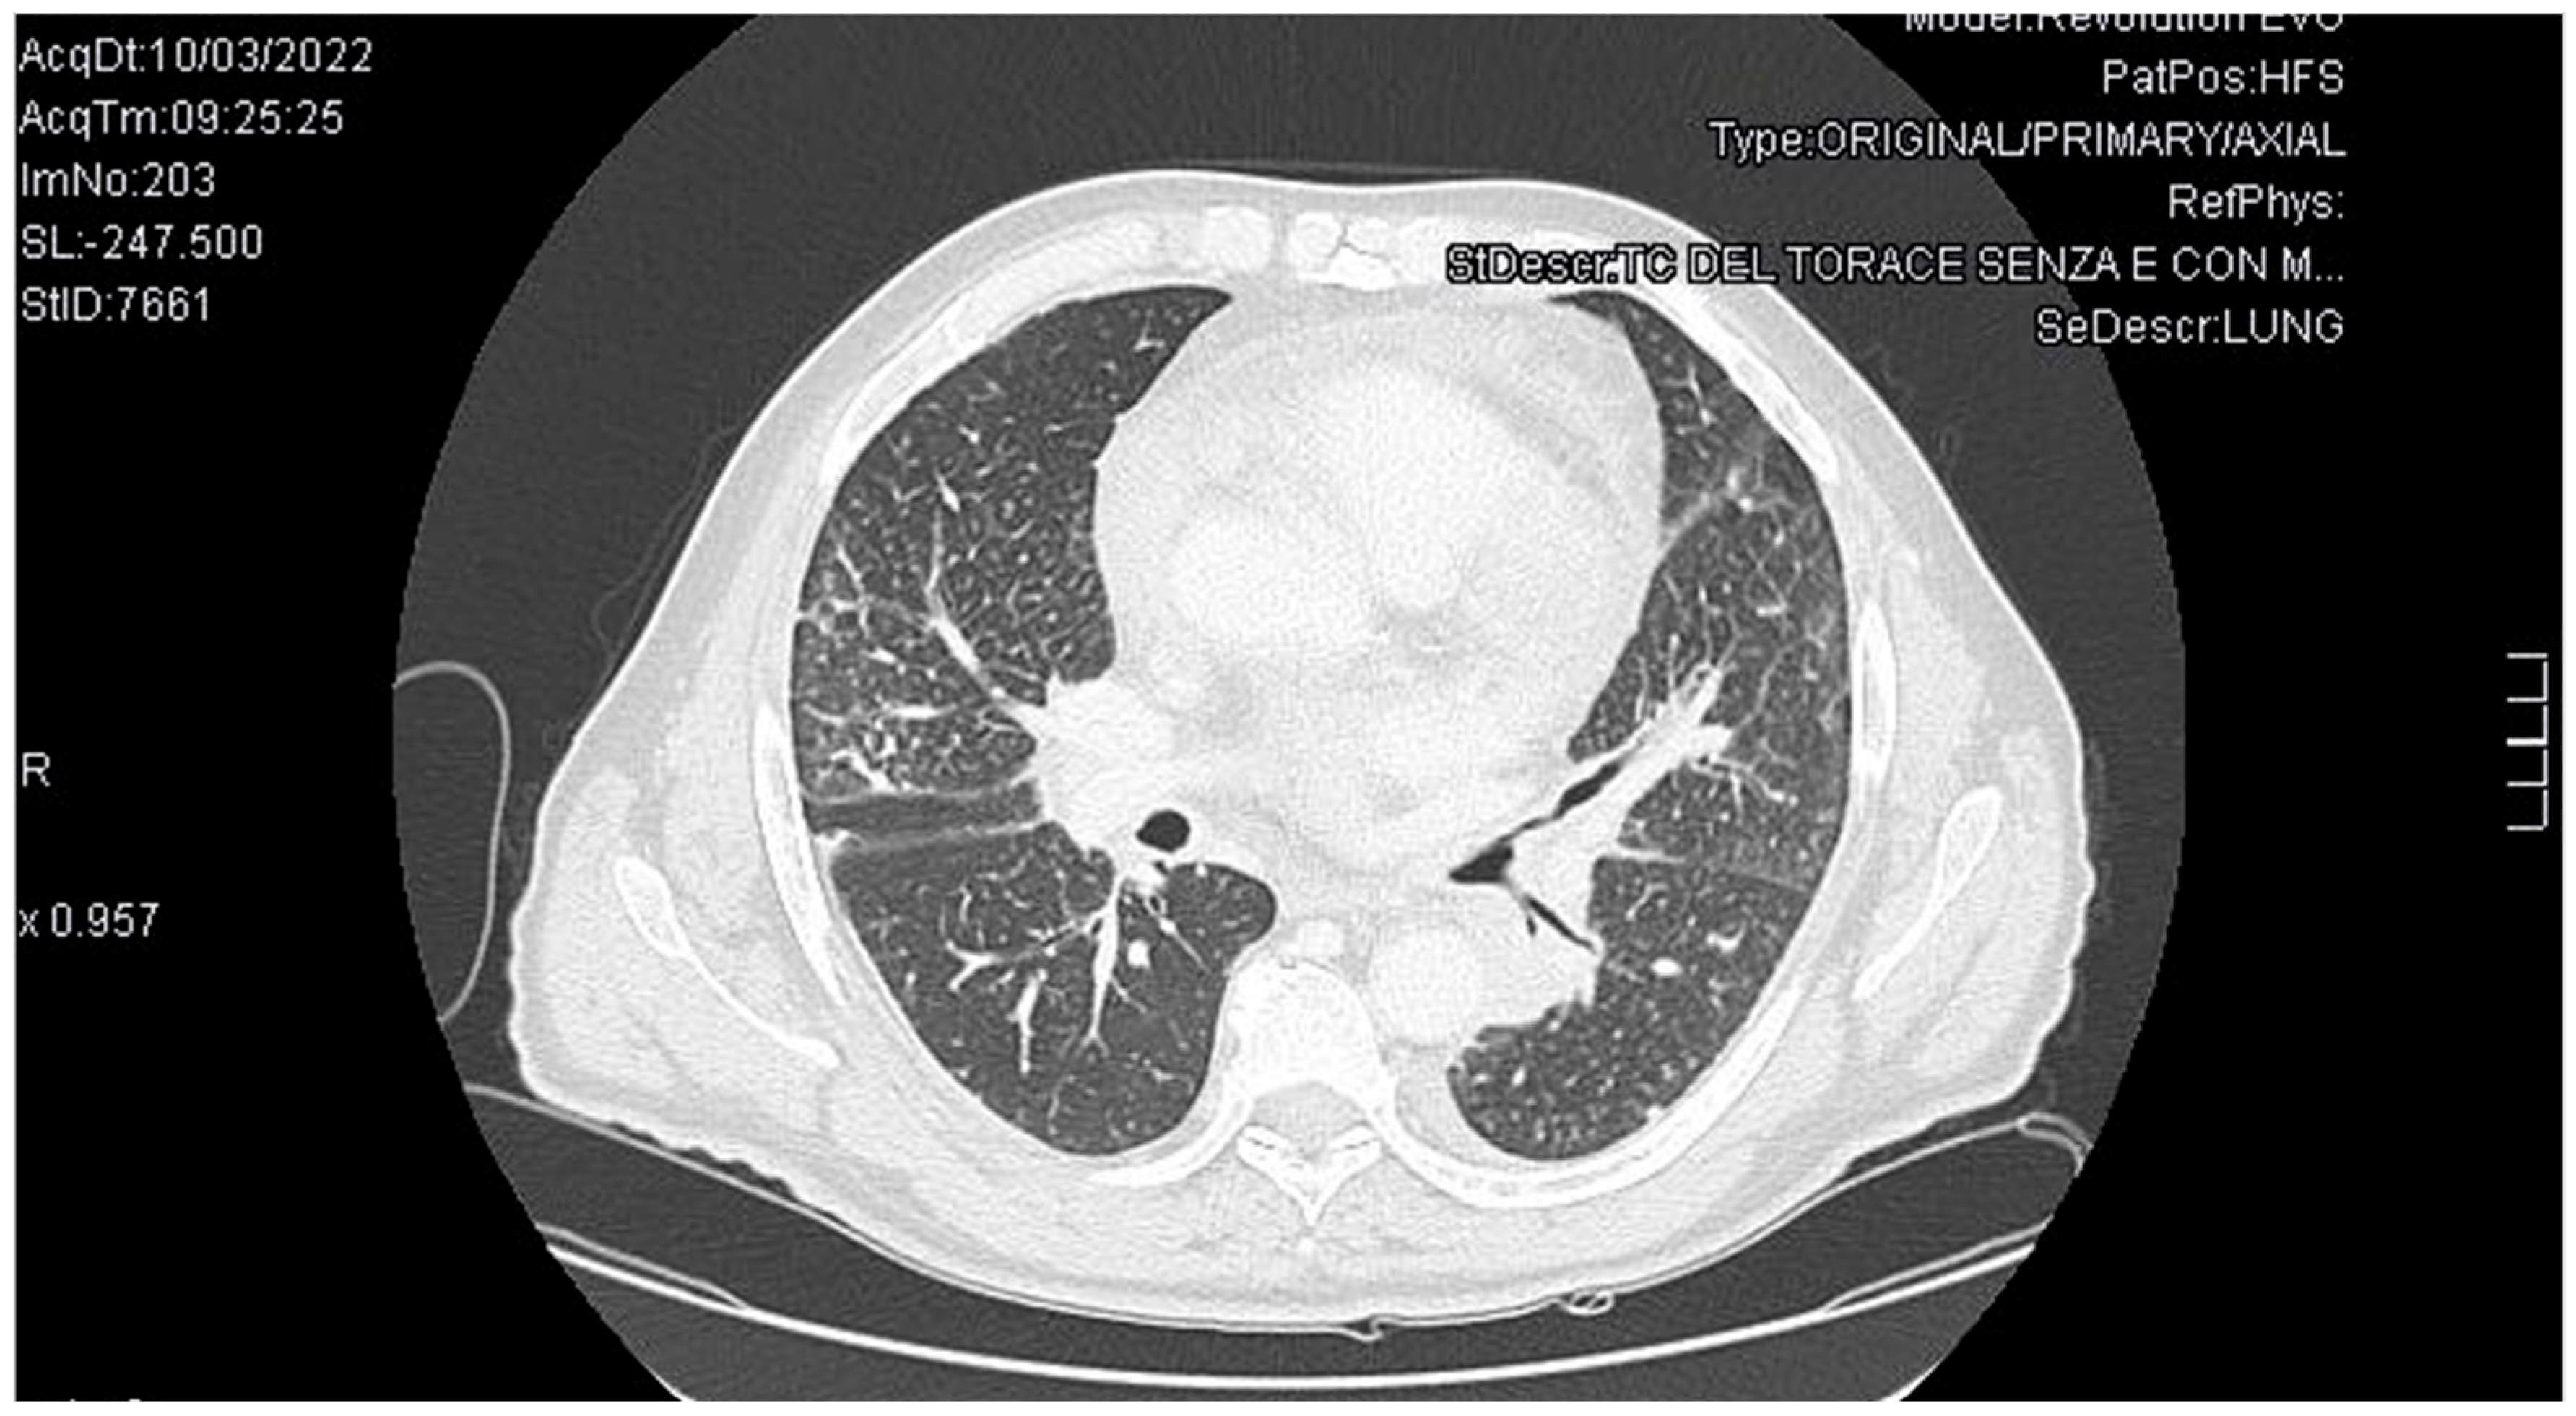

2. Case Presentation